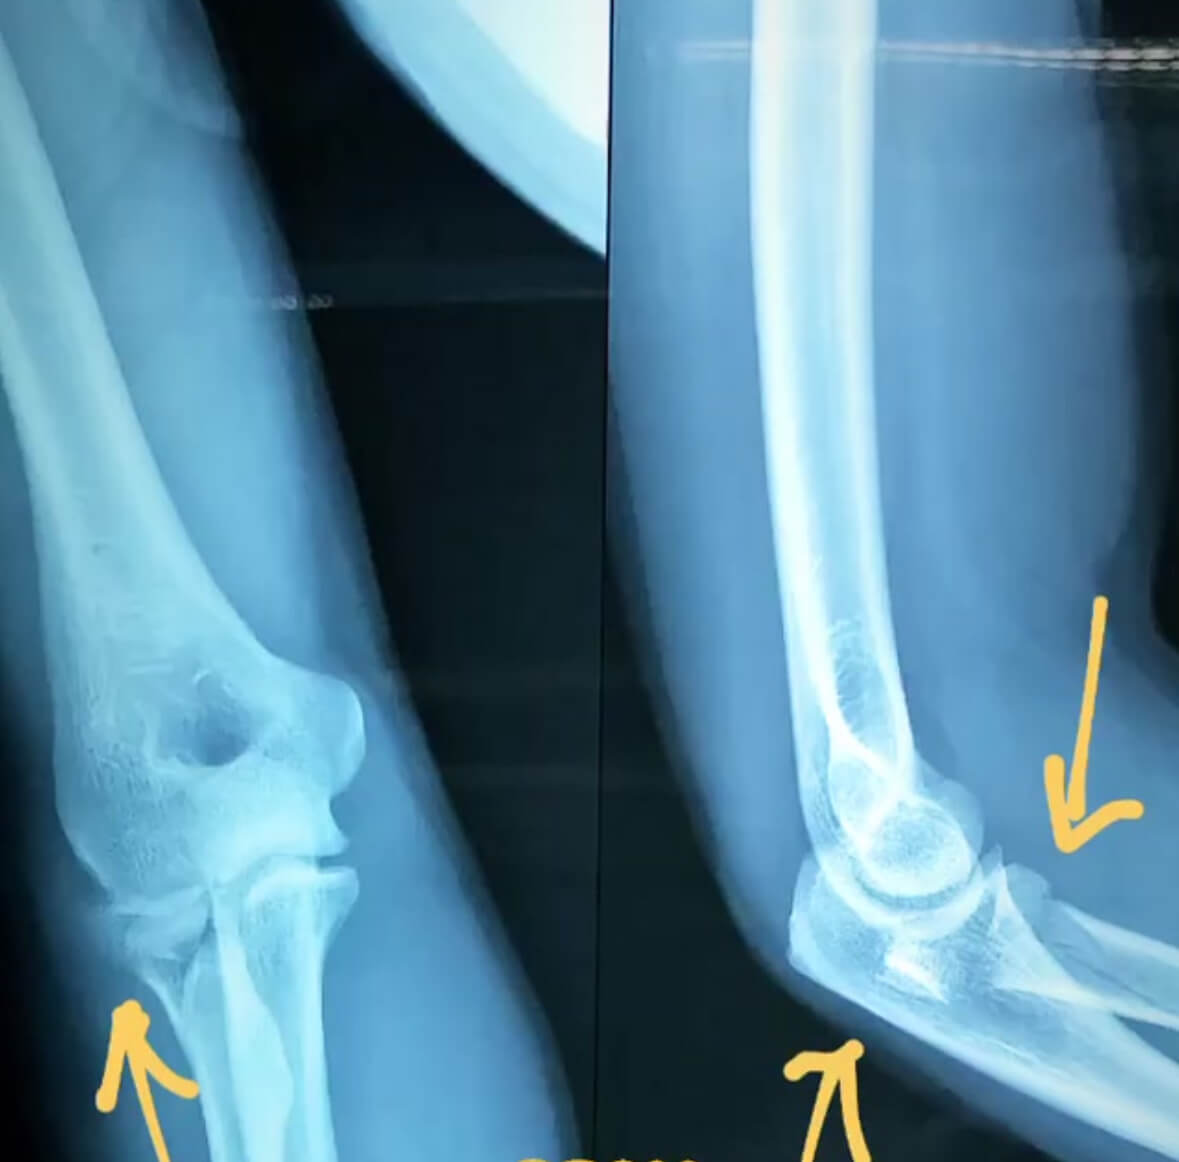

Artroplastia / Reemplazo articular de cúpula radial: En algunas lesiones, seleccionadas, donde la reconstrucción de la cúpula o cabeza de radio no es posible se puede colocar prótesis de la cabeza radial para preservar el espacio y limitar las secuelas en el resto del miembro superior.

Fractura multifragmentada de cúpula radial: En estas radiografías se puede observar como luce una fractura aislada de la cabeza de radio. Según el trazo o su clasificación se indicará tratamiento desde portar un cabestrillo, síntesis o cirugía para restaurar su forma y dar estabilidad e incluso una sustitución de la cúpula radial.